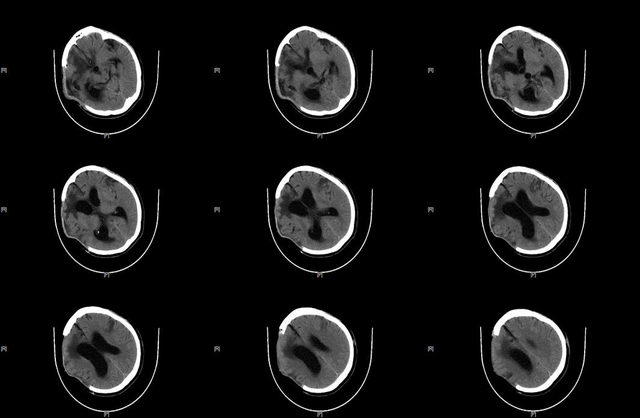

▲SCS(脊髓电刺激)术前,复查头颅CT:血肿已吸收

▲ST-SCS术后CT:电极位置良好

术后复查CT电极位置良好,1天后开始刺激,频率70Hz,脉宽120,电压1.5V,循环模式:15min on/15min off,工作时间8am-8pm。定期进行CRS-R评分。